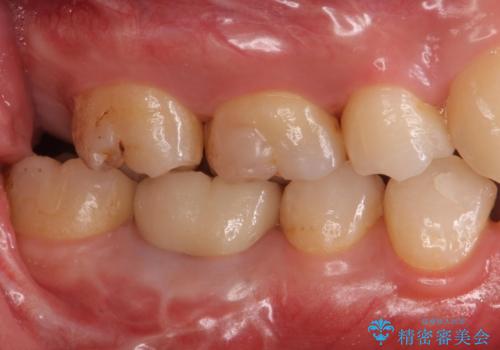

治療後は症状も改善し、半年後の経過も良好です。